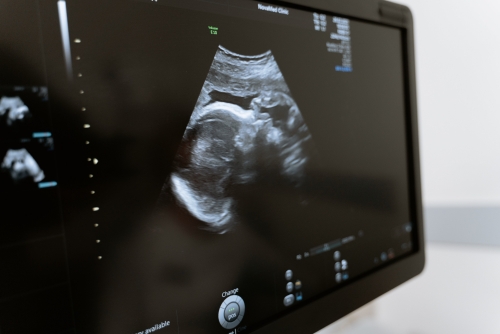

上肢血管超聲檢查是通過(guò)超聲檢查血管壁、血管內(nèi)血流情況的技術(shù)。一般情況下,上肢血管超聲檢查可用于診斷動(dòng)脈硬化、靜脈狹窄、動(dòng)靜脈瘺、血栓閉塞性脈管炎、靜脈血栓形成等疾病。